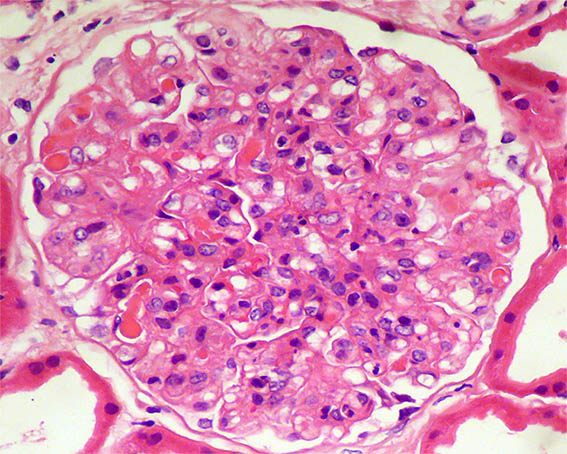

A 62-year-old woman is evaluated for erythema on both legs that has been developing for several weeks. There is no personal pathological history. On physical examination, they found systemic arterial hypertension, edema of the lower limbs, purpuric lesions on both legs, and Raynaud's phenomenon. In paraclinical tests, the hemoleukogram is normal; serum creatinine: 2.1 mg/dL, BUN: 39 mg/dL. ANA, anti-DNA, and ANCA: negative. C3: 82 mg/dL (84-180) and C4: 4.1 mg/dL (12-40). HIV and hepatotropic viruses: negative. In urinalysis there is microhematuria, leukocytes: 5/hpf, proteinuria: 4.2 g/24 hours, with mild hypoalbuminemia.

Figure 1. H&E, X400.